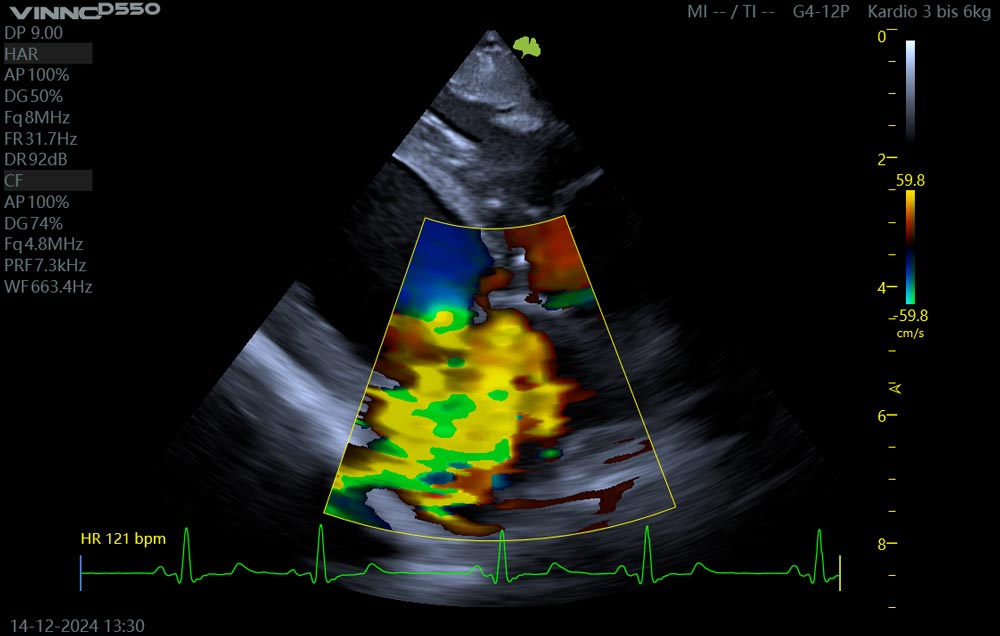

Die Untersuchung des Herzens mittels Ultraschall, Echokardiographie genannt, ermöglicht eine präzise Darstellung der Herzstrukturen und der Herzleistung. Wir können die Herzklappen der beiden Kammersysteme genau darstellen, ihre Dichtigkeit mit dem Farbdoppler untersuchen und die Auswurfleistung des Herzens mit dem Spektraldoppler hochauflösend darstellen. Ein mitlaufendes EKG zeigt genau, wann sich Klappen schließen, wie sich der Herzmuskel kontrahiert und vieles mehr.